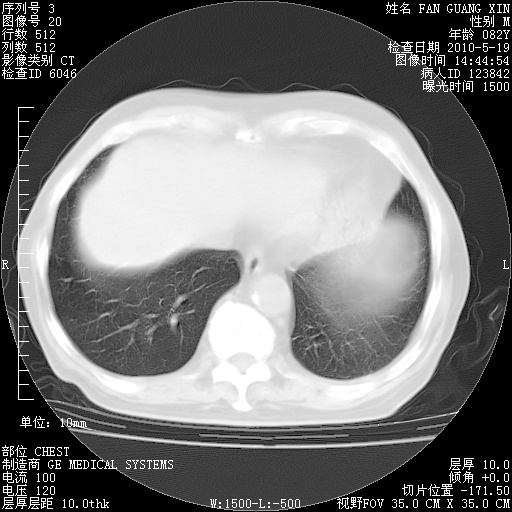

复查肺部CT,明显好转。为什么发热呢?

治疗3周后的肺部CT